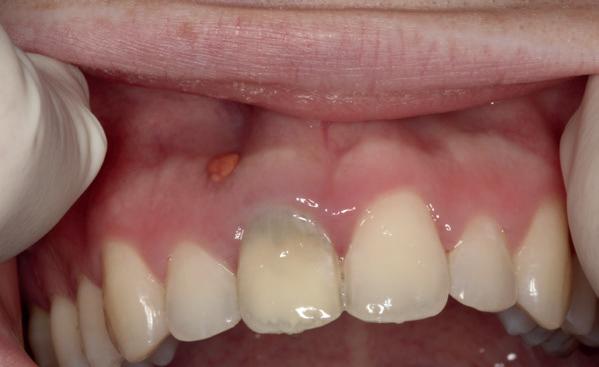

Tijdens het verwijderen van het membraan is het botvolume klinisch waarneembaar en blijkt dat er voldoende bot is om het implantaat te kunnen plaat-

sen. Tijdens deze procedure wordt er ook een free gingival graft van het palatum gehaald. Deze wordt buccaal aangebracht van de 22 en 23 om zo de recessie zoveel mogelijk te bedekken en de papil tussen de 22 en 23 van meer volume te voorzien.

De flap en graft worden met poly-propelene 6.0 hechtingen gefixeerd. De tijdelijke reconstructie wordt herplaatst (foto 17-20).

Na 4-6 weken kan het aangebrachte healing abutment worden vervangen door een tijdelijk abutment. Deze wordt aan de kunststof reconstructie verbonden om zo de gingiva ter plaatse van de 22 te vormen. Zo lijkt het of er geen implantaat maar nog steeds een wortel aanwezig is, wat het esthetisch eindresultaat ten goede zal komen (foto 21-23). Vanaf 4-6 maanden ziet het weefsel er gezond uit. Nu kan met de uiteindelijke restauratiefase worden gestart (foto 24 en 25).